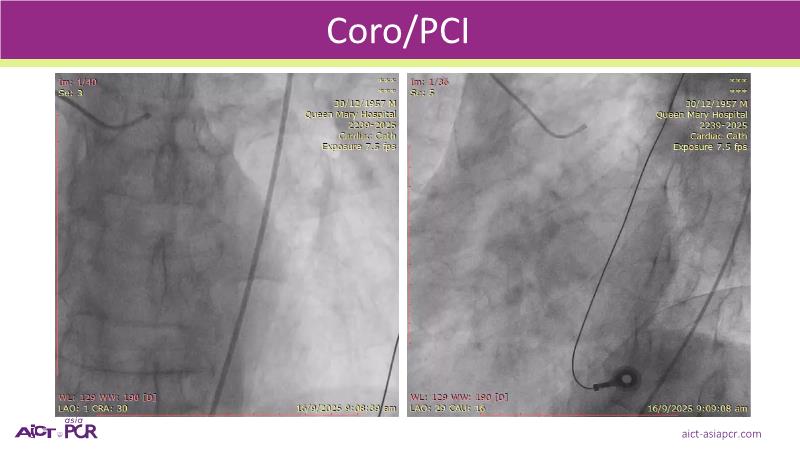

Focus on the evolving role of drug-coated balloons (DCB) in complex PCI, extending their use beyond traditional indications to challenging coronary lesions and high-risk patient populations. This session reviews clinical data from the SCAAR Prevail registry and discusses the evidence journey supporting broader advocacy for DCB in bifurcations, ACS, STEMI, multivessel disease, diabetes, and calcified lesions.